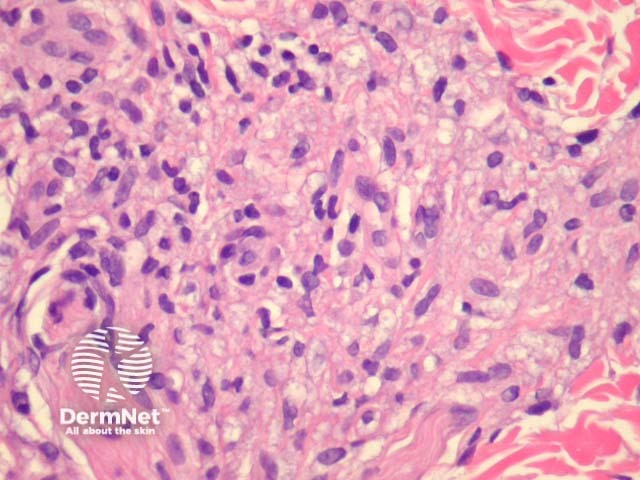

Lepromatous leprosy – Underneath a normal epidermis and grenz zone, there are sheets or clusters of macrophages (figure 1). The macrophages have an abundant pink to pale cytoplasm which corresponds to numerous intracellular (parasitized) organisms (figure 2). The associated infiltrate is usually sparse and mainly lymphocytic. In older lesions, the macrophages may have a bubbly cytoplasm (figure 2). As opposed to tuberculoid leprosy, there are not well-formed granulomas or infiltration of nerves.

Figure 2